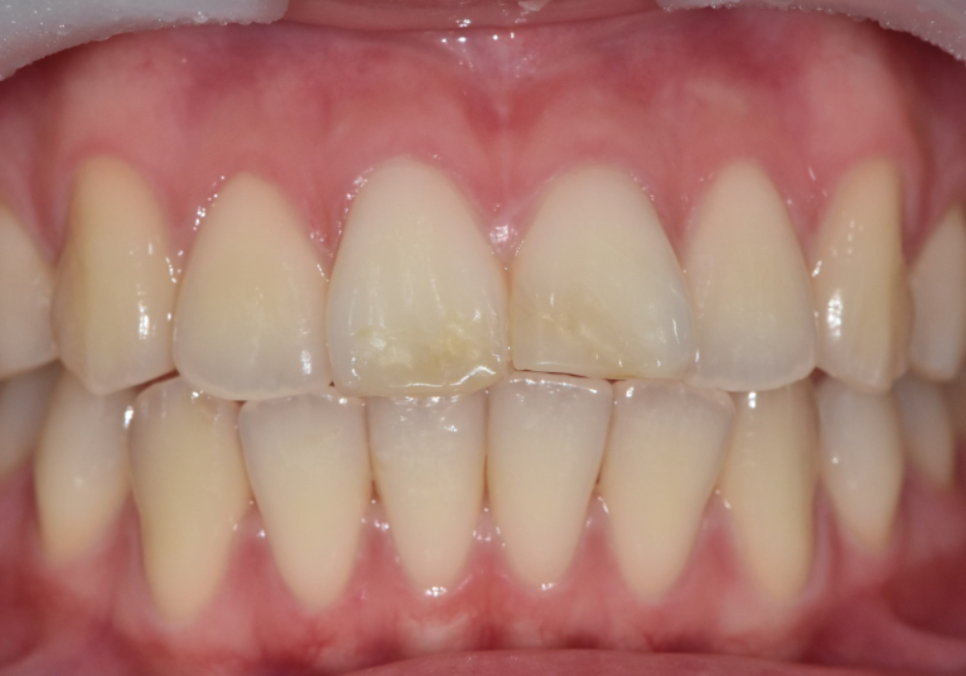

오늘 소개할 환자분도

어릴 때부터 절단교합을 갖고 계셨습니다.

한 번 앞니가 깨진 뒤 레진으로 여러 번 수복했지만

씹을 때마다 같은 자리에 힘이 실리면서

또 깨지고, 또 변색되는 상황이 반복됐습니다.

최근에는 레진이 다시 깨지면서

오른쪽과 왼쪽 앞니 길이가 다르게 보이고

앞니가 살짝 앞으로 뻗어 보이는 돌출감도 겹쳐

웃을 때마다 더 신경 쓰인다며 내원하셨습니다.

250203(전) 250410(후)

최종 라미네이트를 부착한 모습입니다.

· 양쪽 앞니 길이가 가지런해지고

· 앞으로 뻗어 보이던 느낌도 자연스럽게 완화되고

· 절단교합에서도 힘을 덜 받도록 안정적인 공간이 확보되었습니다.